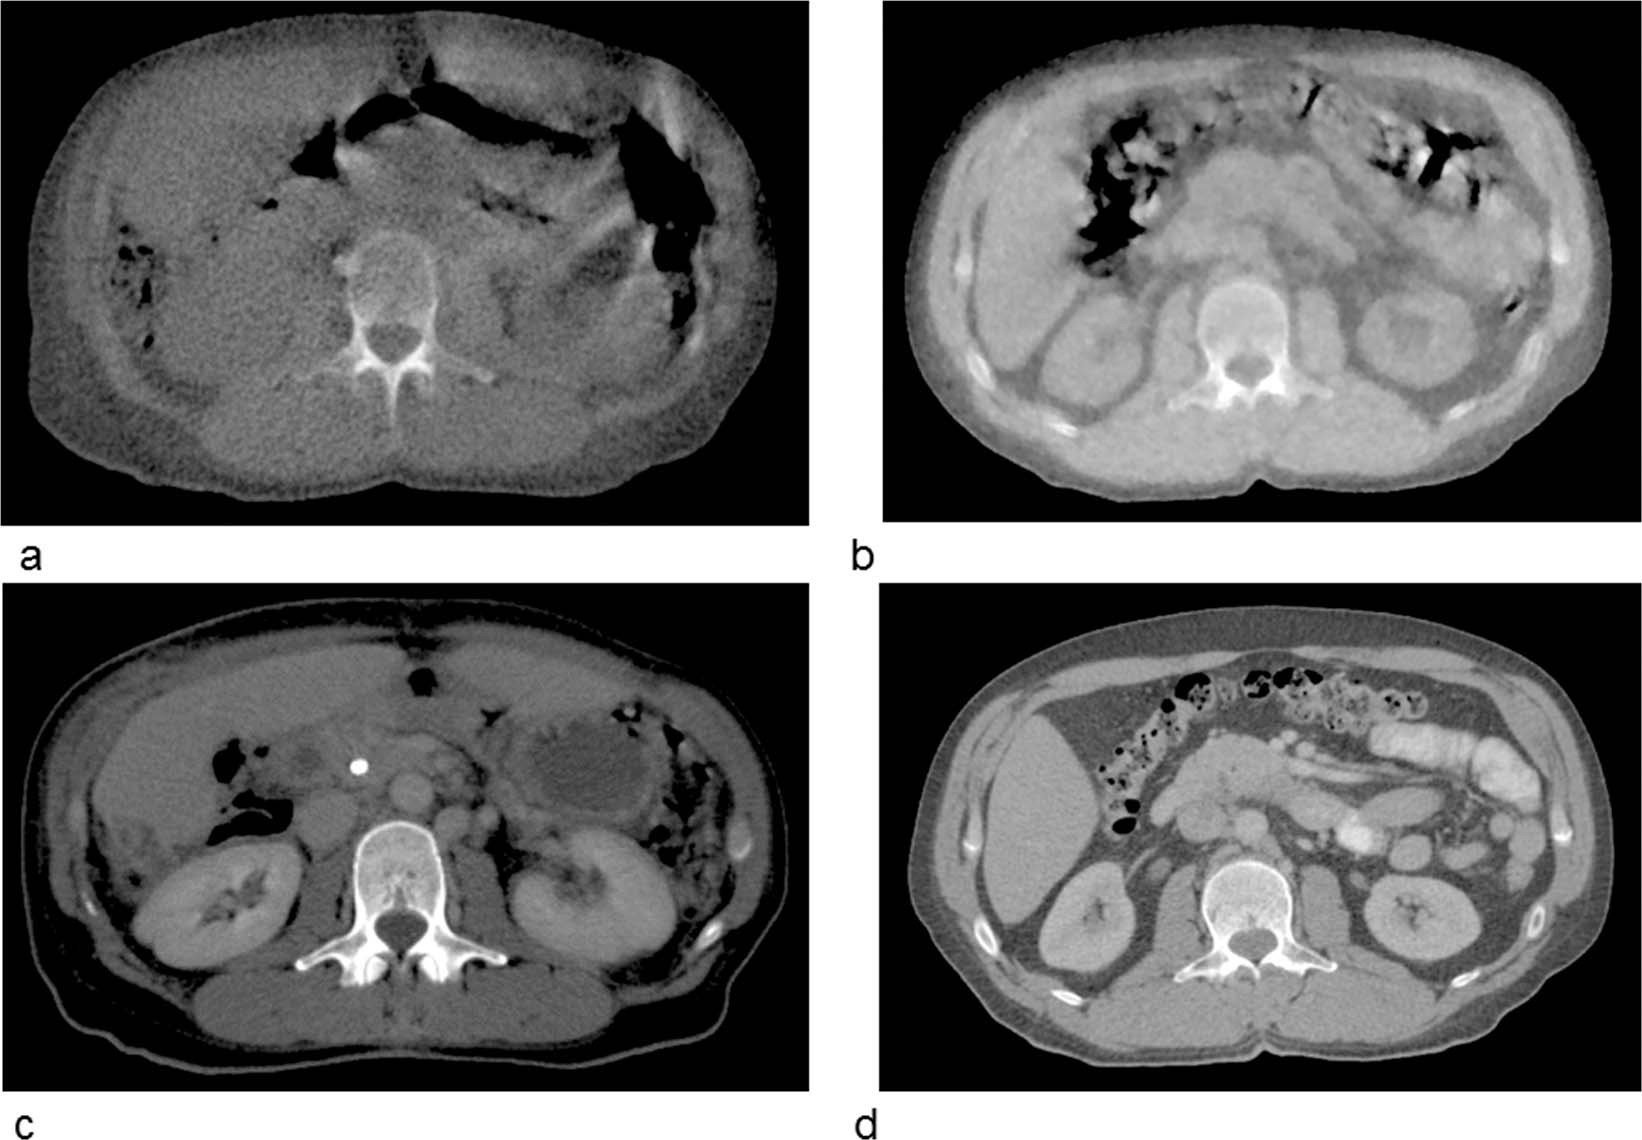

Differences in the image quality of MVCTs of Hi-ART device (a) and the Radixact tomotherapy system (b). In the second row (c) and (d) show the planning kilovoltage CTs for comparison.